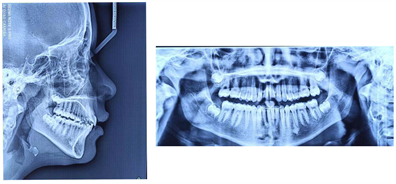

An 8-year-old patient reported to the Department of Dento-Facial Orthopedics of the Dental Consultation and Treatment Center (CCTD) of the Ibn Rochd University Hospital in Casablanca, Morocco, with an aesthetic chief complaint which was projection of the maxillary incisors. He was also experiencing significant school bullying related to his teeth. The functional examination shows an atypical swallowing with interposition of the lower lip, and parents report that the child has allergic rhinitis that has been treated and monitored. Clinical examination (Figure 6) showed a convex profile with accentuated labiomental groove and short cervico-chin distance. The patient was in the mixed dentition stage. Concerning the inter-arch relationship we recorded a Class II molars and canines relation, with 11 mm of overjet and 4 mm of overbite. He had diastema between 53/12, 12/11, 63/22, 41/31 and occlusal fracture on the 21. The panoramic radiograph (Figure 7) showed normal bone and tooth forms without developing third molars. Cephalometric analysis revealed a Class II skeletal base (ANB = 9.2˚) with normotrusive maxilla, retrusive mandible (SNA = 84.7˚, SNB 75.6˚). Moreover, the patient had a skeletally long face (GoGn/SN = 35˚, FMA = 30.9˚). In addition, the upper incisor was prooclined (I/NA = 28.9˚/3mm), and lower incisors was normoclined (I/NB = 20˚/4mm).

Figure 7. Pre-treatment lateral cephalogram and panoramic radiograph.